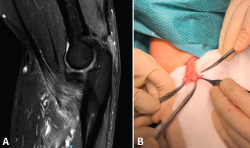

En cuanto a las lesiones parciales, el tratamiento conservador es una opción razonable para aquellos pacientes con lesiones de bajo grado (< 50%)(14). Un periodo corto de inmovilización, seguido de ganancia progresiva del balance articular y de la potenciación en rehabilitación puede alcanzar buenos resultados(31). Todavía está en cuestión cuánto tiempo debe durar un tratamiento conservador antes de considerarlo fallido y proponer al paciente un tratamiento quirúrgico consistente en desinserción completa (Figura 5) seguido de reinserción del tendón, ya que tampoco hay evidencia acerca la progresión de las roturas parciales a totales(32).

Figura 5. A: corte sagital de resonancia nuclear magnética en el que se identifica una lesión parcial del bíceps distal con engrosamiento de las fibras; B: imagen quirúrgica tras desinsertar la parte indemne.